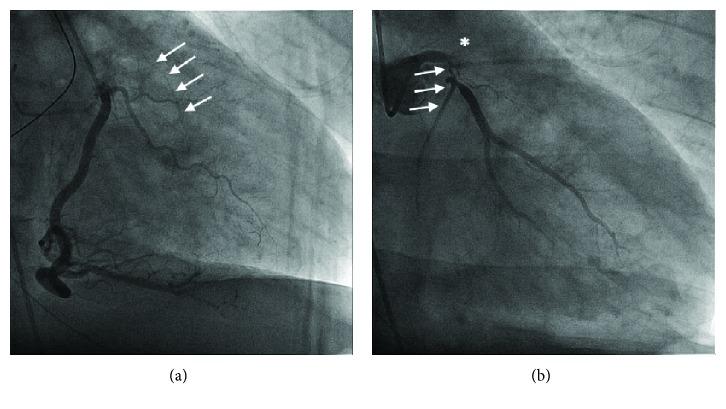

Acute coronary syndromes (ACS) usually occur in patients with multiple cardiac risk factors. In young adults, drug use and hypercoagulable states are common causes for ACS presentations. We report a case of a man in his early 30s who was diagnosed with polycythemia vera (PV) and had a cardiac arrest due to an anterolateral ST elevation myocardial infarction. We discuss his unique management and review the evidence on the management of arterial thromboembolism in PV patients.

急性冠状动脉综合征(ACS)通常发生在有多种心脏危险因素的患者中。在年轻成年人中,药物使用和高凝状态是ACS表现的常见原因。我们报告一例30岁出头的男性病例,该患者被诊断为真性红细胞增多症(PV),并因前侧壁ST段抬高型心肌梗死发生心脏骤停。我们讨论了他独特的治疗方法,并回顾了关于PV患者动脉血栓栓塞治疗的证据。